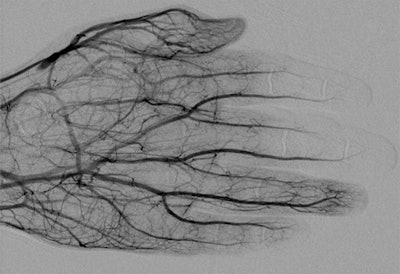

Lee and Higgins sought to evaluate the efficacy of intra-arterial and intravenous tPA therapies to treat these injuries and reduce the need for amputation. They reviewed 157 studies, finally including 16 that described using intra-arterial and intravenous tPA. The studies consisted of 209 patients with 1,109 digits at risk of amputation. In 15 of the 16 studies, patients were initially evaluated using digital subtraction angiography (DSA) or triple-phase bone scans.

- Use DSA to assess areas of impaired perfusion. DSA can also be used to start intra-arterial infusion therapy.